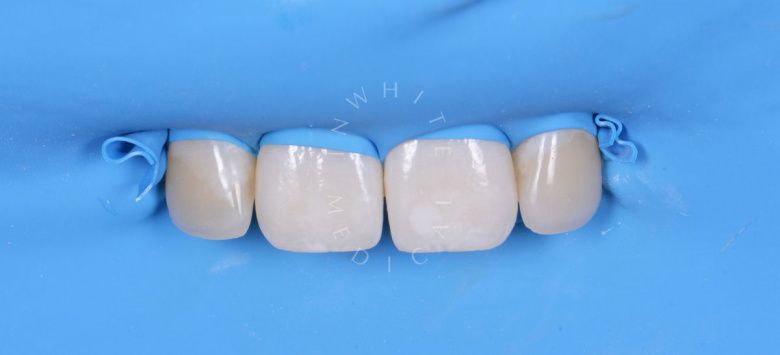

Лечение фиссурного кариеса под увеличением

Восстановление зуба пломбой (лечение фиссурного кариеса) / А16.07.002.015

19 360 ₽